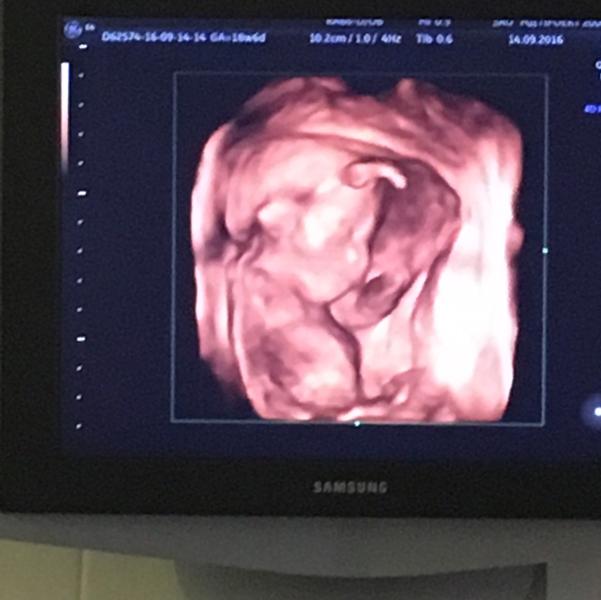

Мой малыш растёт.... ❤️❤️❤️Только вот тонус совсем замучал... Прописали гинипрал... И капельницы капаю магнезию😫.... Но пока что то не вижу улучшений ....

Я тоже с тонусом борюсь с 16 недели:/ Магнезия мне помогает, но не сразу и лежать нужно долго, по 5-6 часов пока капают. Фотка ми ми мишная)